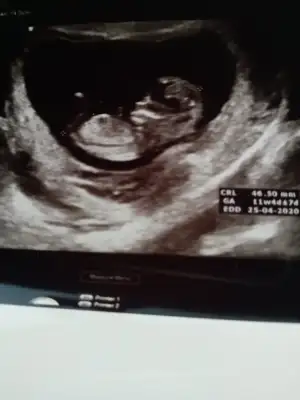

Merhaba kizlr. Devlte gittim anca bu kdarlik gorntu var. Sizce neye benzio. Tam 11 haftlik

Sırtı dönmüş başka varmımerhaba kızlarr bana da tahminleriniz nedir teşekkür ederim şimdiden:))))))Eki Görüntüle 2543467

Heyecan işte canımm dün usg de uyuyordu yavrum öksürüp zorla hareket ettirdimKesin mi derken tahmin Canım yüzde 50 benden çok ikra yu dikkate al